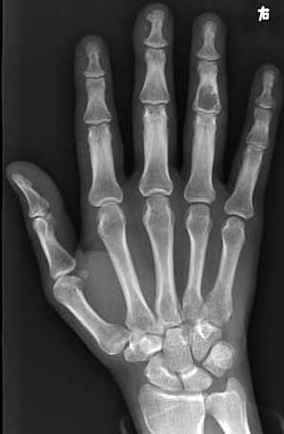

以下是引用ctm在2005-4-19 18:28:02的发言:[br]发生于手指指骨,膨胀性生长,囊状低密度影,其中沙砾样钙化。骨皮质变薄硬化。典型内生骨软骨瘤。

以下是引用枫叶在2005-4-21 0:03:53的发言:[br][br] \"支持血管球瘤\"______不知真人怎就这样想了???[br]我还是支持\"典型\"的内生软骨瘤!!! [br] [br]